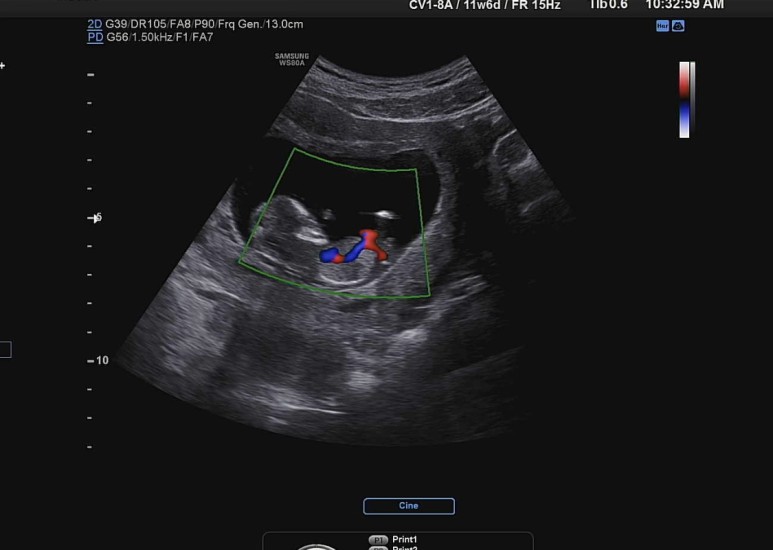

심장으로 혈액이 잘 흘러 들어가고 있는지 색깔을 통해 확인.